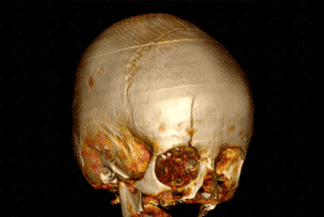

Texto alternativo para a imagem Figura 1. Créditos: Dra Elazir Mota - Rio de Janeiro/RJ

Descrição da lesão: Traumatismo cranioencefálico na criança. Tomografia computadorizada do crânio com reconstrução tridimensional (3D): presença de volumoso hematoma subgaleal na região frontal direita (figura 1, setas vermelhas). Na reconstrução tridimensional, nota-se o traço de fratura na mesma topografia com extensão ao teto da órbita deste lado, sem desalinhamento ósseo significativo (figura 2 e 3).